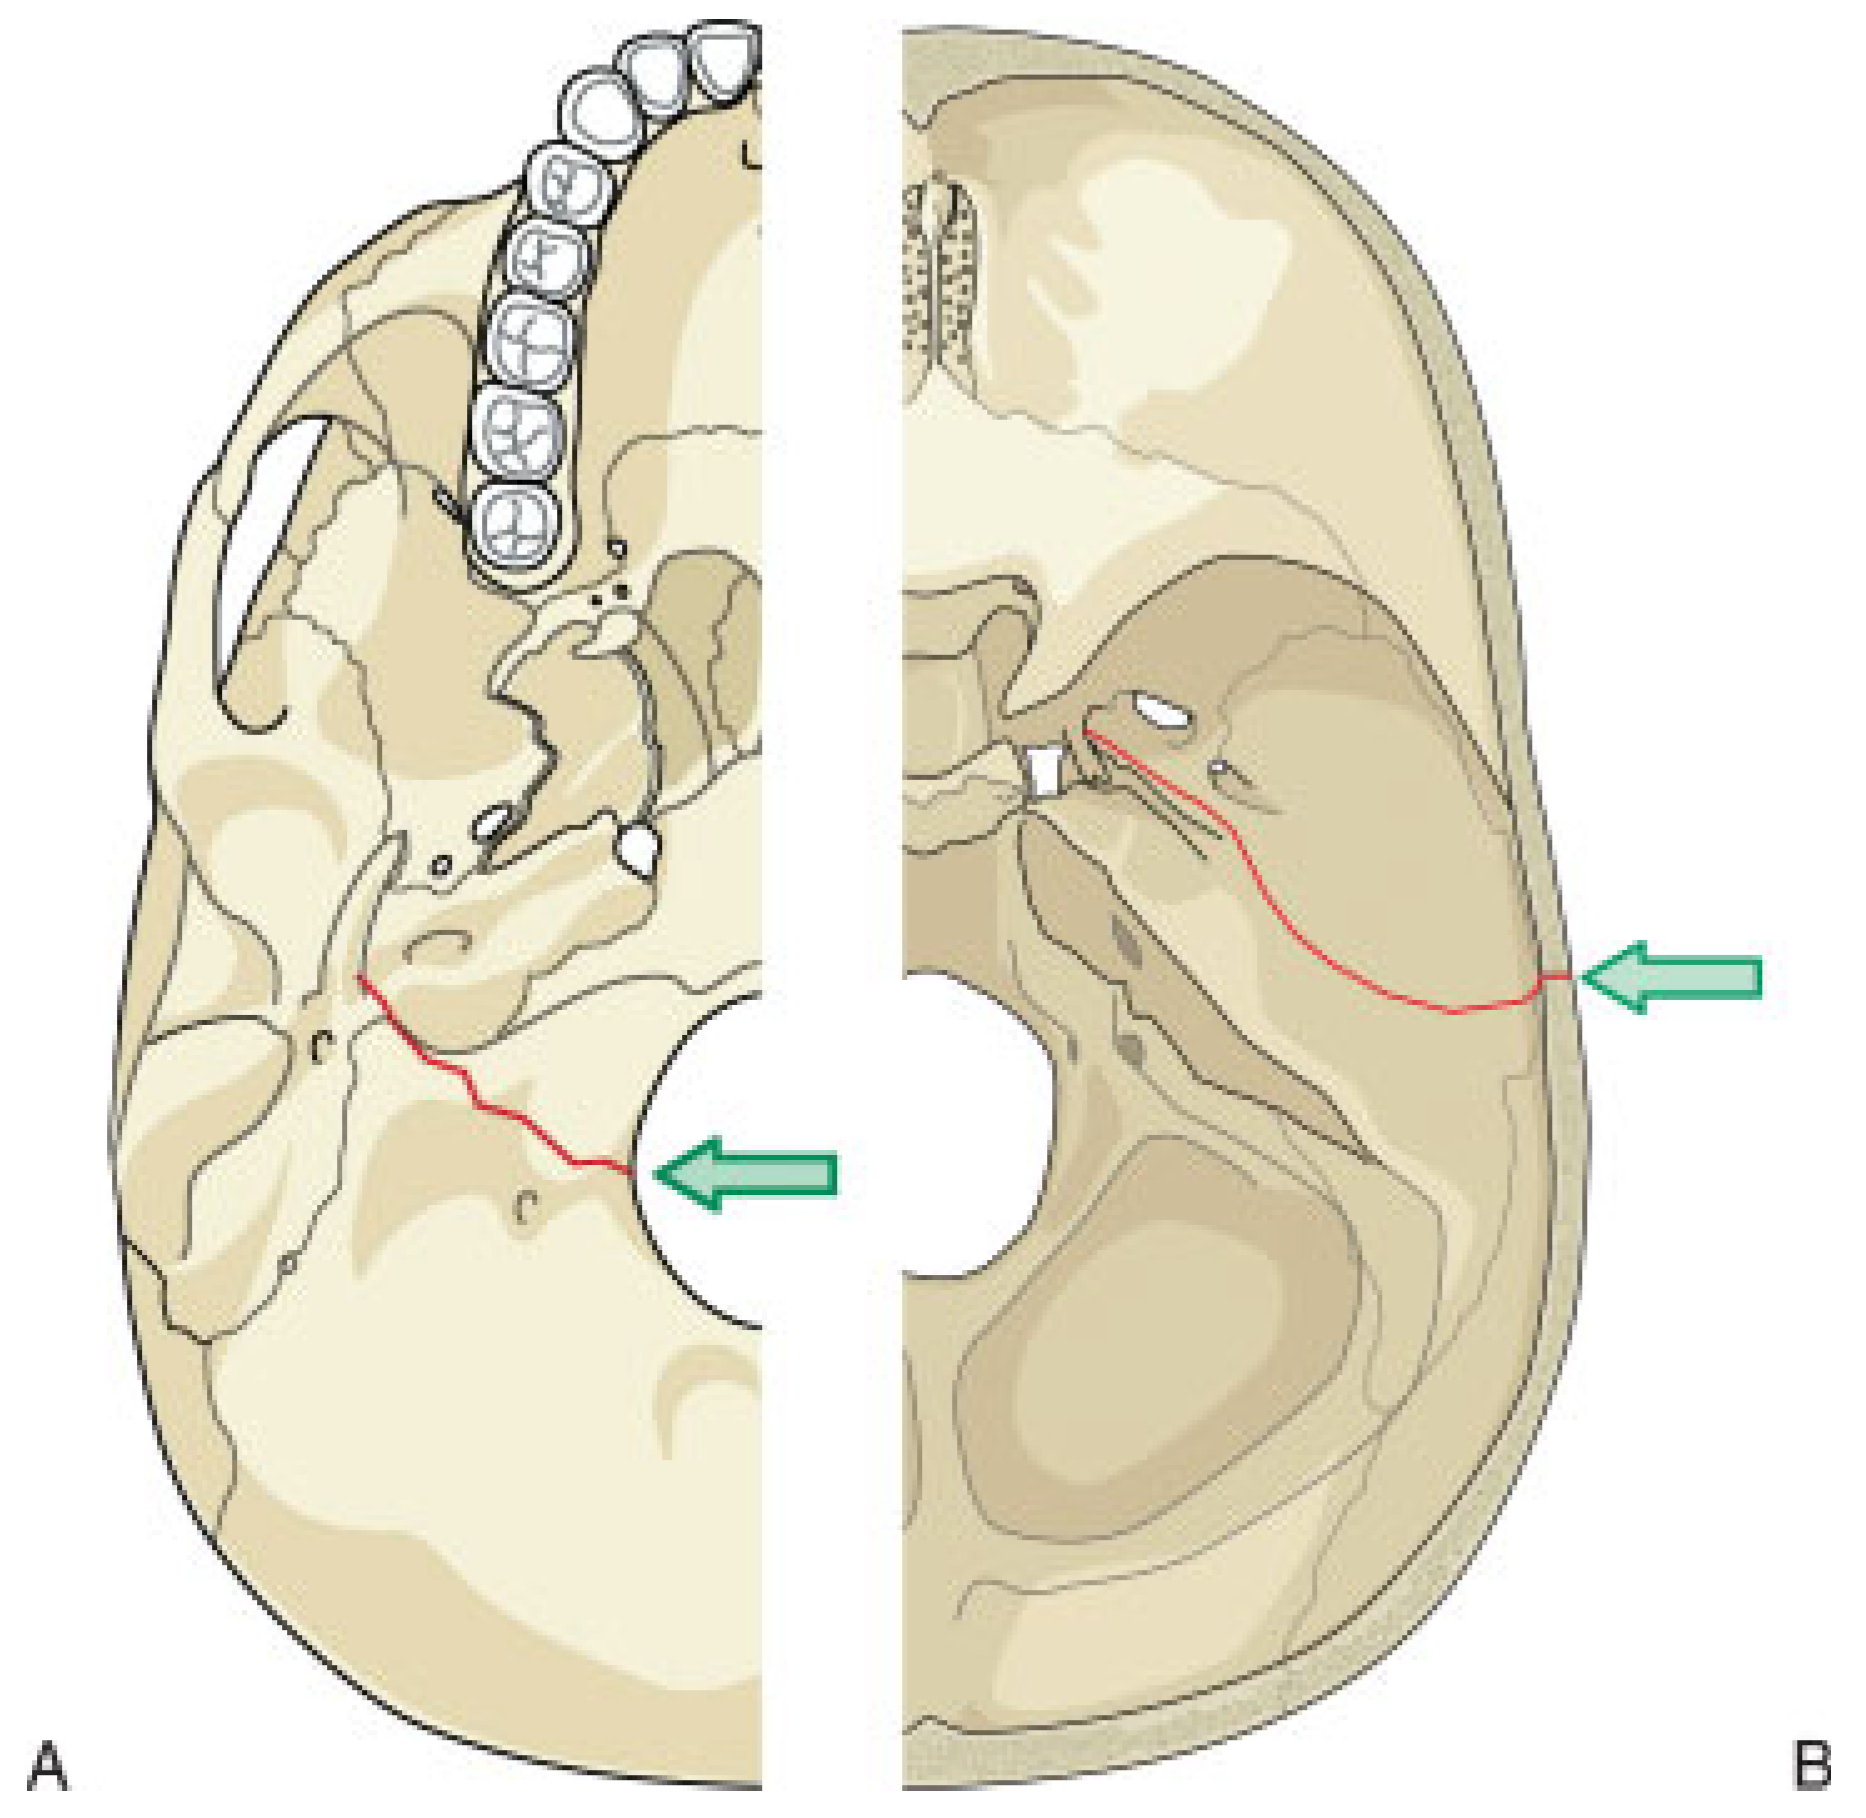

High-resolution CT scans with bone algorithms are the standard in diagnosis of temporal bone trauma. Axial and coronal thin-section CT scans can establish fracture sites in most cases, and more than one-third of fractures detected by CT are missed by clinical diagnosis alone [12]. In general, the fracture lines run parallel to the line of the blow delivered and extend through foramina, which weaken the bone. Fractures may be single or multiple and are classically referred to as longitudinal or transverse (Figure 6 and Figure 7), although careful observation demonstrates that most are actually oblique. The original terminology persists as it predicts well-known sequelae.

Approximately 70 to 80% of temporal bone fractures are longitudinal, resulting from a blow to the temporal or parietal region of the skull [13]. These fractures follow the path of least resistance, which usually leads through the petrosquamous suture line and continues anterior to the otic capsule. Involvement of the middle ear causes frequent hemotympanum and ossicular disrution, resulting in conductive hearing loss. The facial nerve is involved in 15 to 20% of these fractures.

Transverse fractures are less common and result from forces generated along the anterior-posterior axis, usually blows to the back of the head. Fractures begin at the jugular foramen and extend across the petrous pyramid to the area of the foramen spinosum and foramen lacerum. Sensorineural hearing loss and vertigo are secondary to direct injury of the inner ear, and occur in up to 50% of these fractures. The facial nerve is involved in nearly half of these fractures as well.

Figure 6. Diagram of common fracture patterns of the temporal bone. Transverse fractures (A) result most often from a blow to the back of the head. The fracture extends from the jugular foramen through the petrous pyramid to the foramen spinosum and foramen lacerum. Longitudinal fractures (B) result most often from a blow to the side of the head. The fracture extends from the squamous portion of the temporal bone to the carotid and jugular foramina.